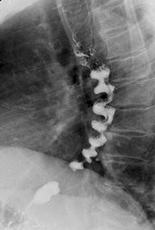

Acid ingestion (HCL). Diffuse burns and contraction/shrinkage of both the esophagus and stomach (Courtesy Dr. V. Penopoulos)